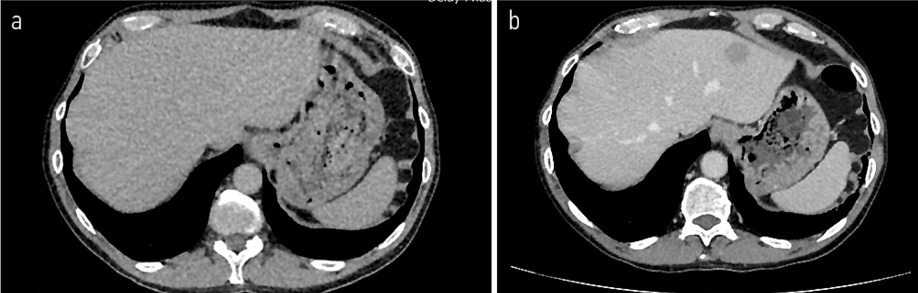

Рис. 9. КТ органов брюшной полости от 02.11.2022 в сравнении с КТ от 11.01.22. КТ-картина билобарного очагового поражения печени: в S2 – до 20×23 см, на границе S2|3 – до 13×15 см, в S6 – 8×11 мм.

Fig. 9. Abdominal CT scan dated 02.11.2022 in comparison with CT scan dated 11.01.22. Bilobar focal lesions of the liver: in S2 – up to 20×23 cm, at the border of S2|3 – up to 13×15 cm, in S6 – 8×11 mm.

Рис. 10. КТ органов брюшной полости от 02.11.2022 в сравнении с КТ от 11.01.2022. КТ-картина билобарного очагового поражения печени: в S2 – до 20×23 см, на границе S2|3 – до 13×15 см, в S6 – 8×11 мм.

Fig. 10. Abdominal CT scan dated 02.11.2022 in comparison with CT scan dated 11.01.2022. Bilobar focal lesions of the liver: in S2 – up to 20×23 cm, at the border of S2|3 – up to 13×15 cm, in S6 – 8×11 mm.

С 08.2022 по 22.12.2022 проведено 6 курсов лекарственного лечения по схеме карбоплатин + иринотекан. По результатам контрольного обследования от 01.2023: отрицательная динамика в виде увеличения размера очагов в костях скелета: в левой подвздошной кости до 29×25 мм (ранее до 25×23 мм) и 38×26 мм (ранее до 33×25 мм), в крыле подвздошной кости до 56×19 мм (ранее 27×22 мм), в боковой массе крестца слева до 28×23 мм (ранее 27×22 мм) и появления новых мелких очагов в бедренных костях до 5 мм и в телах LII–IV позвонков диаметром до 3 мм; билобарного очагового поражения печени: в S2 – до 20×23 см, на границе S2|3 – до 13×15 см, в S6 – 8×11 мм (рис. 9, 10).